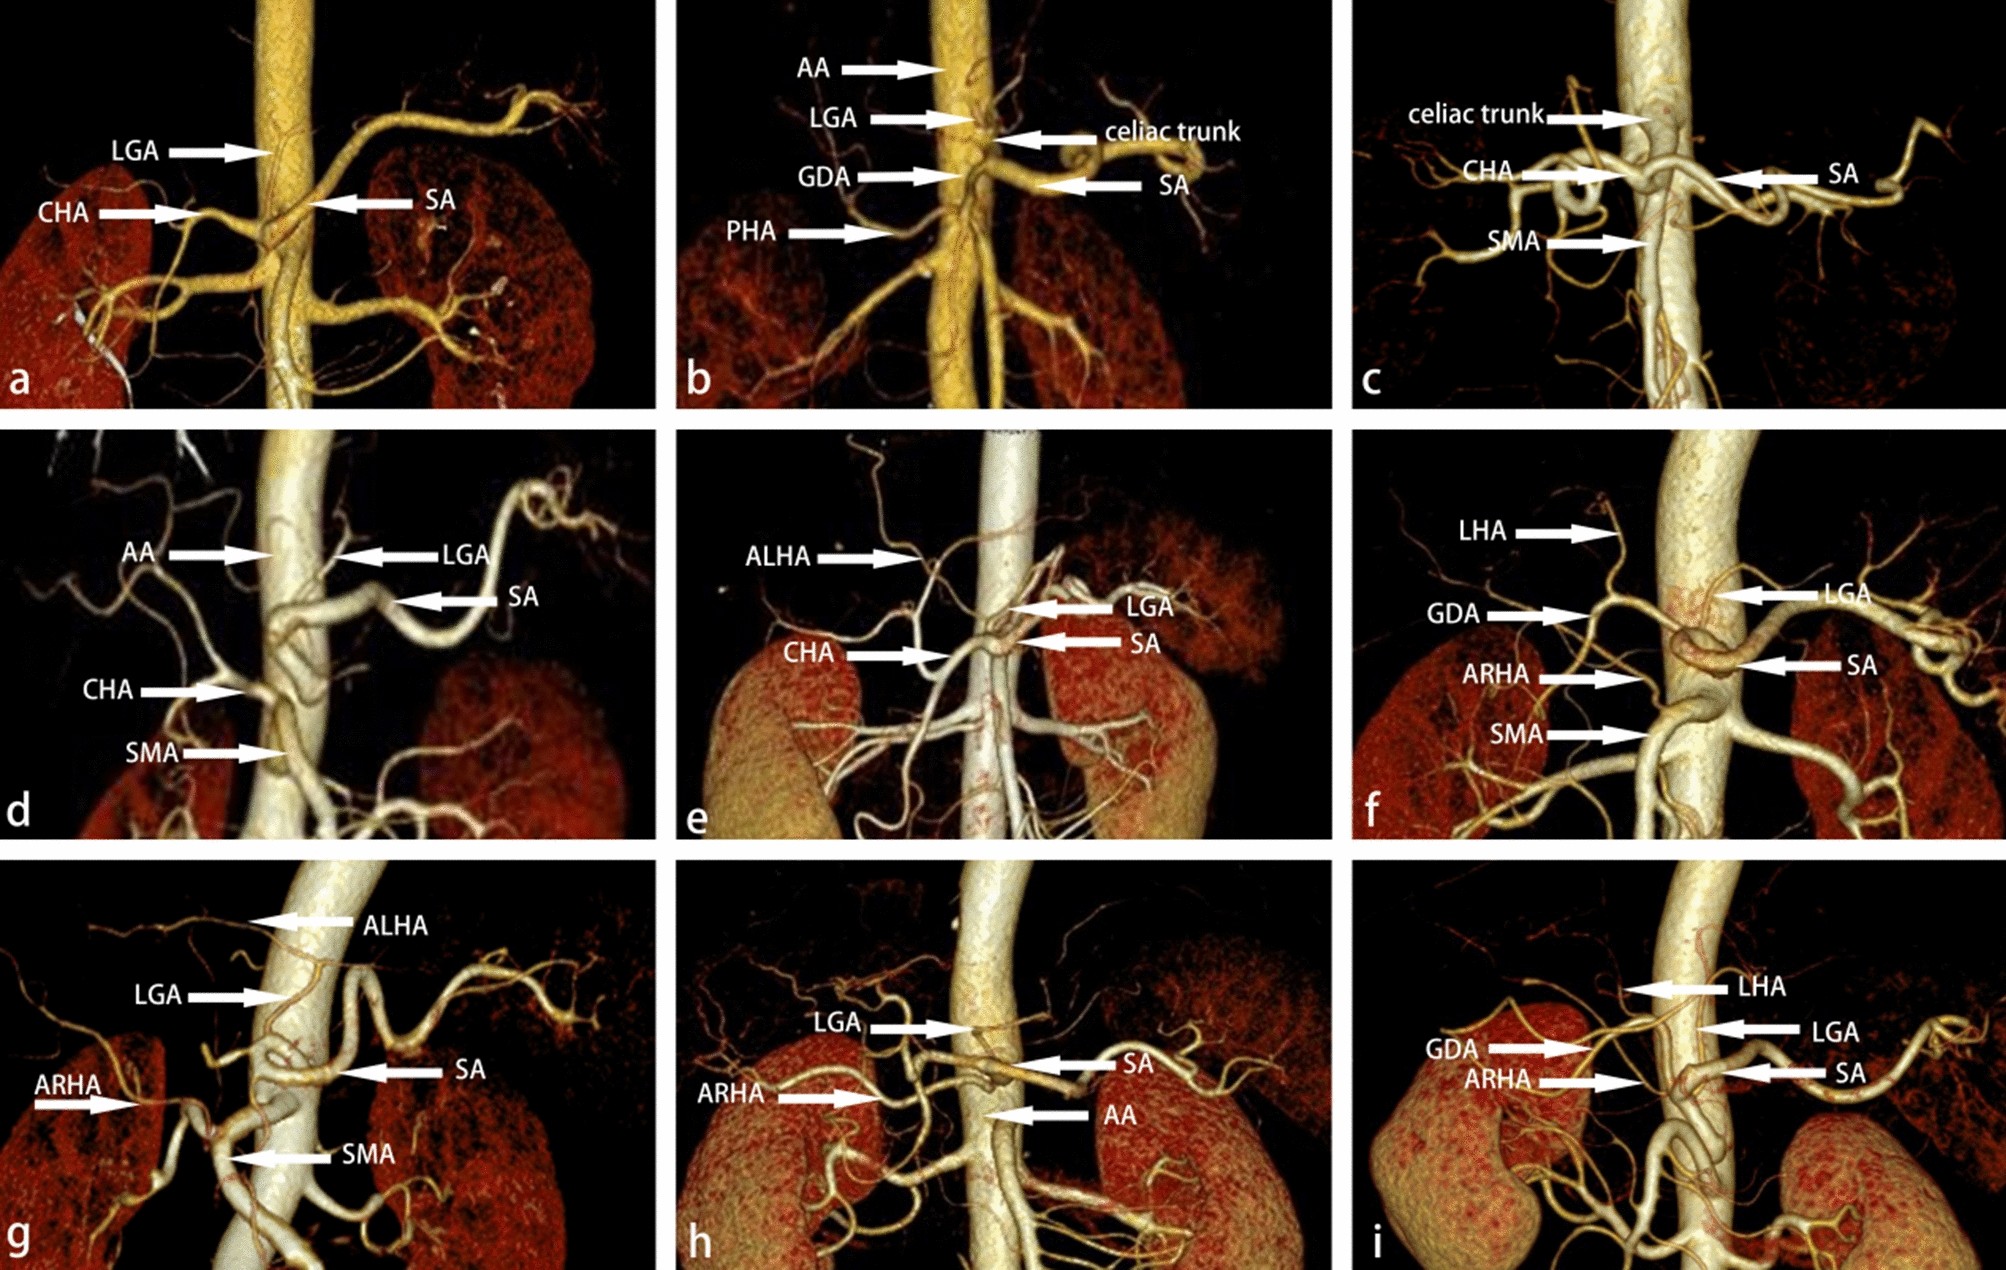

Figure 3

Classification of the celiac trunk. (a) LGA, CHA, and SA all originated from the celiac trunk. (b) LGA originated from AA, CHA and SA originated from the celiac trunk. (c) CHA, SA, SMA, and LGA originated from the celiac trunk. (d) CHA originated from SMA. (e) ALHA from LGA. (f) The ARHA originated from SMA. (g) ARHA from SMA, ALHA from LGA coexist. (h) In this case, ARHA from AA. (i) In this case, ARHA from the celiac trunk.